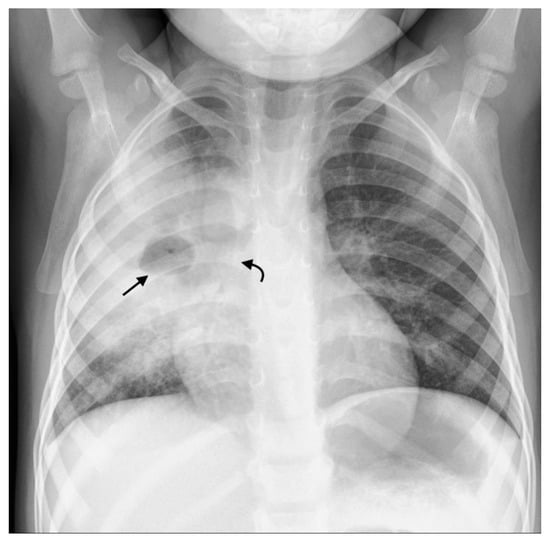

Figure 6. Consolidation and miliary TB. Frontal AP and lateral chest radiographs in a 3-year-old boy with confirmed disseminated TB. This child did not receive BCG vaccination. (a) Frontal AP and (b) lateral chest radiographs demonstrating right upper lobe consolidation with air bronchograms (black arrow) limited by the horizontal fissure (white arrows), as well as parenchymal miliary TB nodules.

Consolidation can occur via several distinct mechanisms. Firstly, it may represent primary parenchymal PTB disease, which then spreads to regional lymph nodes. Conversely, in primary progressive TB disease, consolidation can develop as a complication of airway compression or from bronchogenic spread of disease [1,14]. Consolidation is characterized on chest radiographs by air bronchograms and silhouetting of the cardiac, mediastinal, or diaphragmatic margins, depending on the location [5] (Figure 6).

Miliary TB is more common in young or immunocompromised patients [2] occurring secondary to hematogenous spread of the disease. It is characterized on the chest radiograph by the diffusion of small (<2 mm) non-calcified nodules, representing granulomas, appearing throughout the lung parenchyma, frequently in combination with thickened interlobular septal lines [1] (Figure 6). However, in 25–40% of cases, chest radiographs are normal [1]. Miliary nodules occur on CT well before they become visible on chest radiographs [1].